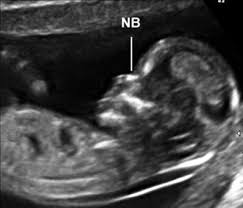

This is because the hormones in the body change based on what stage you are at your pregnancy. This new appointment will also require a new referral from your doctor. There was some confusion because my last period was about december 26 of 2013, but the first week of xxxxxxx i had a very short period and only bled one day. I haven't had any blood tests but based on this measurement have been told that there is a. Nuchal translucency (nt) measurement nuchal translucensy (nt) is the clear space in the tissue of your developing baby's neck. A sonographer will apply a transducer (wand) to the outside of your stomach to measure your baby from crown to rump and check that the fetal age is accurate. This scan has been shown to detect 77% of babies who are born with down syndrome. It might need to be done alone, or it might be able to be done while you're having your dating scan. The ultrasound is done as a transvaginal ultrasound and it measures the thickness of the. You may be told on that day if your nuchal translucency test scored higher than 3.5mm. If i wa 13 weeks at dating scan does this then mean baby only really 11 weeks old? A nuchal translucency ultrasound (commonly called a nuchal scan or nt scan) is an ultrasound performed between 11.5 and 13 weeks 6 days gestation. The nt scan is part of the combined screening test for down syndrome, but your sonographer will also take measurements to confirm your due date.

This raised nt can sometimes be an indicator of a problem in the baby's development, explains arc's jane fisher. This new appointment will also require a new referral from your doctor. The amount of fluid is measured during a nuchal translucency (nt) ultrasound scan: The size of the fetus, from which the gestational age is estimated. What does the conception + 2 weeks mean? And yet, bizarrely, after your dating scan at 12 weeks, your due date can get less accurate the more pregnant you get. Increasingly, though, doctors and midwives are offering women a dating scan before their nt scan. A nuchal translucency ultrasound (commonly called a nuchal scan or nt scan) is an ultrasound performed between 11.5 and 13 weeks 6 days gestation.

Then he or she will locate the nuchal fold and measure its thickness on the screen. You may be offered a dating scan between eight and 10 weeks. I wouldn't take an early scan as read, as it's not your official dating scan anyway. does it get more accurate as you get more pregnant? I am 28 yrs old and pregnant for the first time. The ultrasound is done as a transvaginal ultrasound and it measures the thickness of the. If i wa 13 weeks at dating scan does this then mean baby only really 11 weeks old? This scan has been shown to detect 77% of babies who are born with down syndrome. In case of one patient she tried to do nuchal translucency ultrasound with transabdominal approach but due to maternal body habitus and fetal position she also used transvaginal. A nuchal translucency ultrasound (commonly called a nuchal scan or nt scan) is an ultrasound performed between 11.5 and 13 weeks 6 days gestation. A dating scan might be recommended before 12 weeks to confirm your due date if you are unsure of your last menstrual period or your date of conception. What does the conception + 2 weeks mean? Between 11 weeks and 14 weeks of pregnancy or when your baby measures between 45mm (1.8in) and 84mm (3.3in) all developing babies have some fluid at the back of their neck. What does nt scan report at 12 weeks mean what are the.

This means the baby tests with a high risk yet does not end up having down syndrome. Usually the scan is done through your abdomen but occasionally the nuchal translucency can only be seen by inserting a probe into the vagina. This test measures the size of the clear tissue, called the nuchal translucency, at the back of your baby. Between 11 weeks and 14 weeks of pregnancy or when your baby measures between 45mm (1.8in) and 84mm (3.3in) all developing babies have some fluid at the back of their neck. This scan is carried out from 11 weeks to 13 weeks and six days. I had my scan on wedneday (12 weeks 2 days) and was told that our nuchal measurement was 3.6mm, which was raised. Nuchal translucency refers to the sonographic image showing the fluid accumulation behind the fetus' neck. You may be offered a dating scan between eight and 10 weeks.